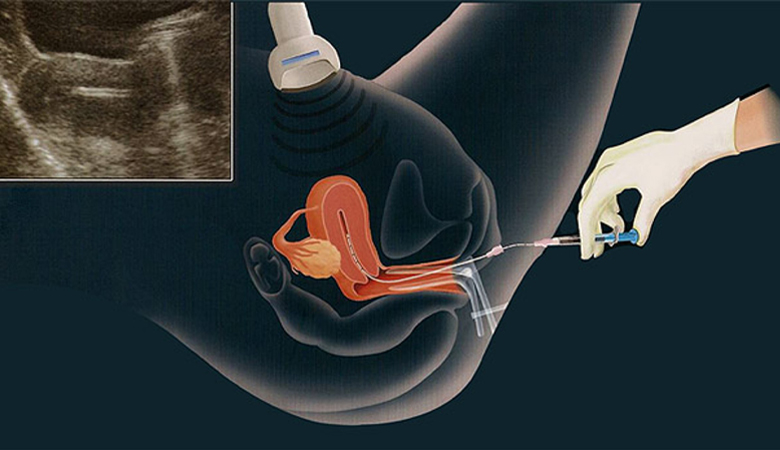

O diagnóstico pré-implantacional é um exame que pode ser feito durante o processo de fertilização in vitro para diagnosticar nos...